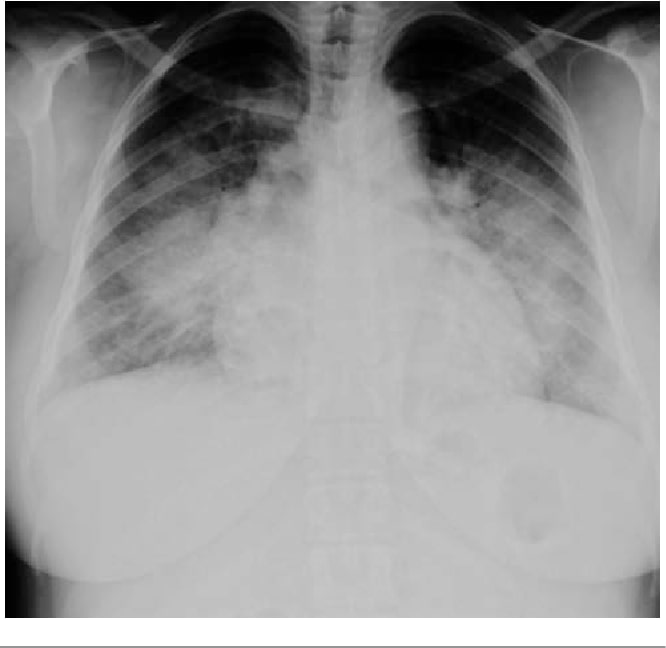

Alice, a 20-year old female with no significant past medical history is brought in by ambulance with worsening upper abdominal pain onset 1 week ago when she woke up. She has felt nauseous and has vomited one time this morning. Two days ago, she began to feel short of breath. She states that it has been getting worse and she is now having trouble lying flat. She was hypertensive with EMS.

A 20-year old female 5 weeks postpartum (G1T1A0) after a cesarean section is brought in by ambulance with worsening upper abdominal pain onset 1 week ago, 2 days of worsening dyspnea and a new severe headache. The patient is found to be increasingly hypertensive and eventually has a seizure. As the patient’s condition deteriorates the team must determine the cause of this patient’s symptoms (pre-eclampsia) and aggressively treatment her symptoms with IV magnesium, IV anti-hypertensives, IV anti-epileptics and eventually, intubation.